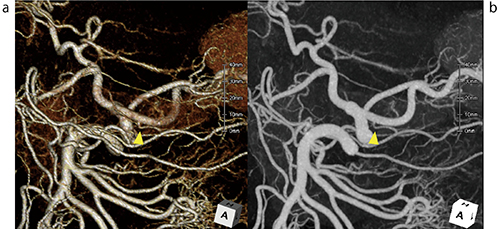

図3 背側膵動脈(dorsal pancreatic artery)の描出(▲)

a:VR画像、b:MIP画像